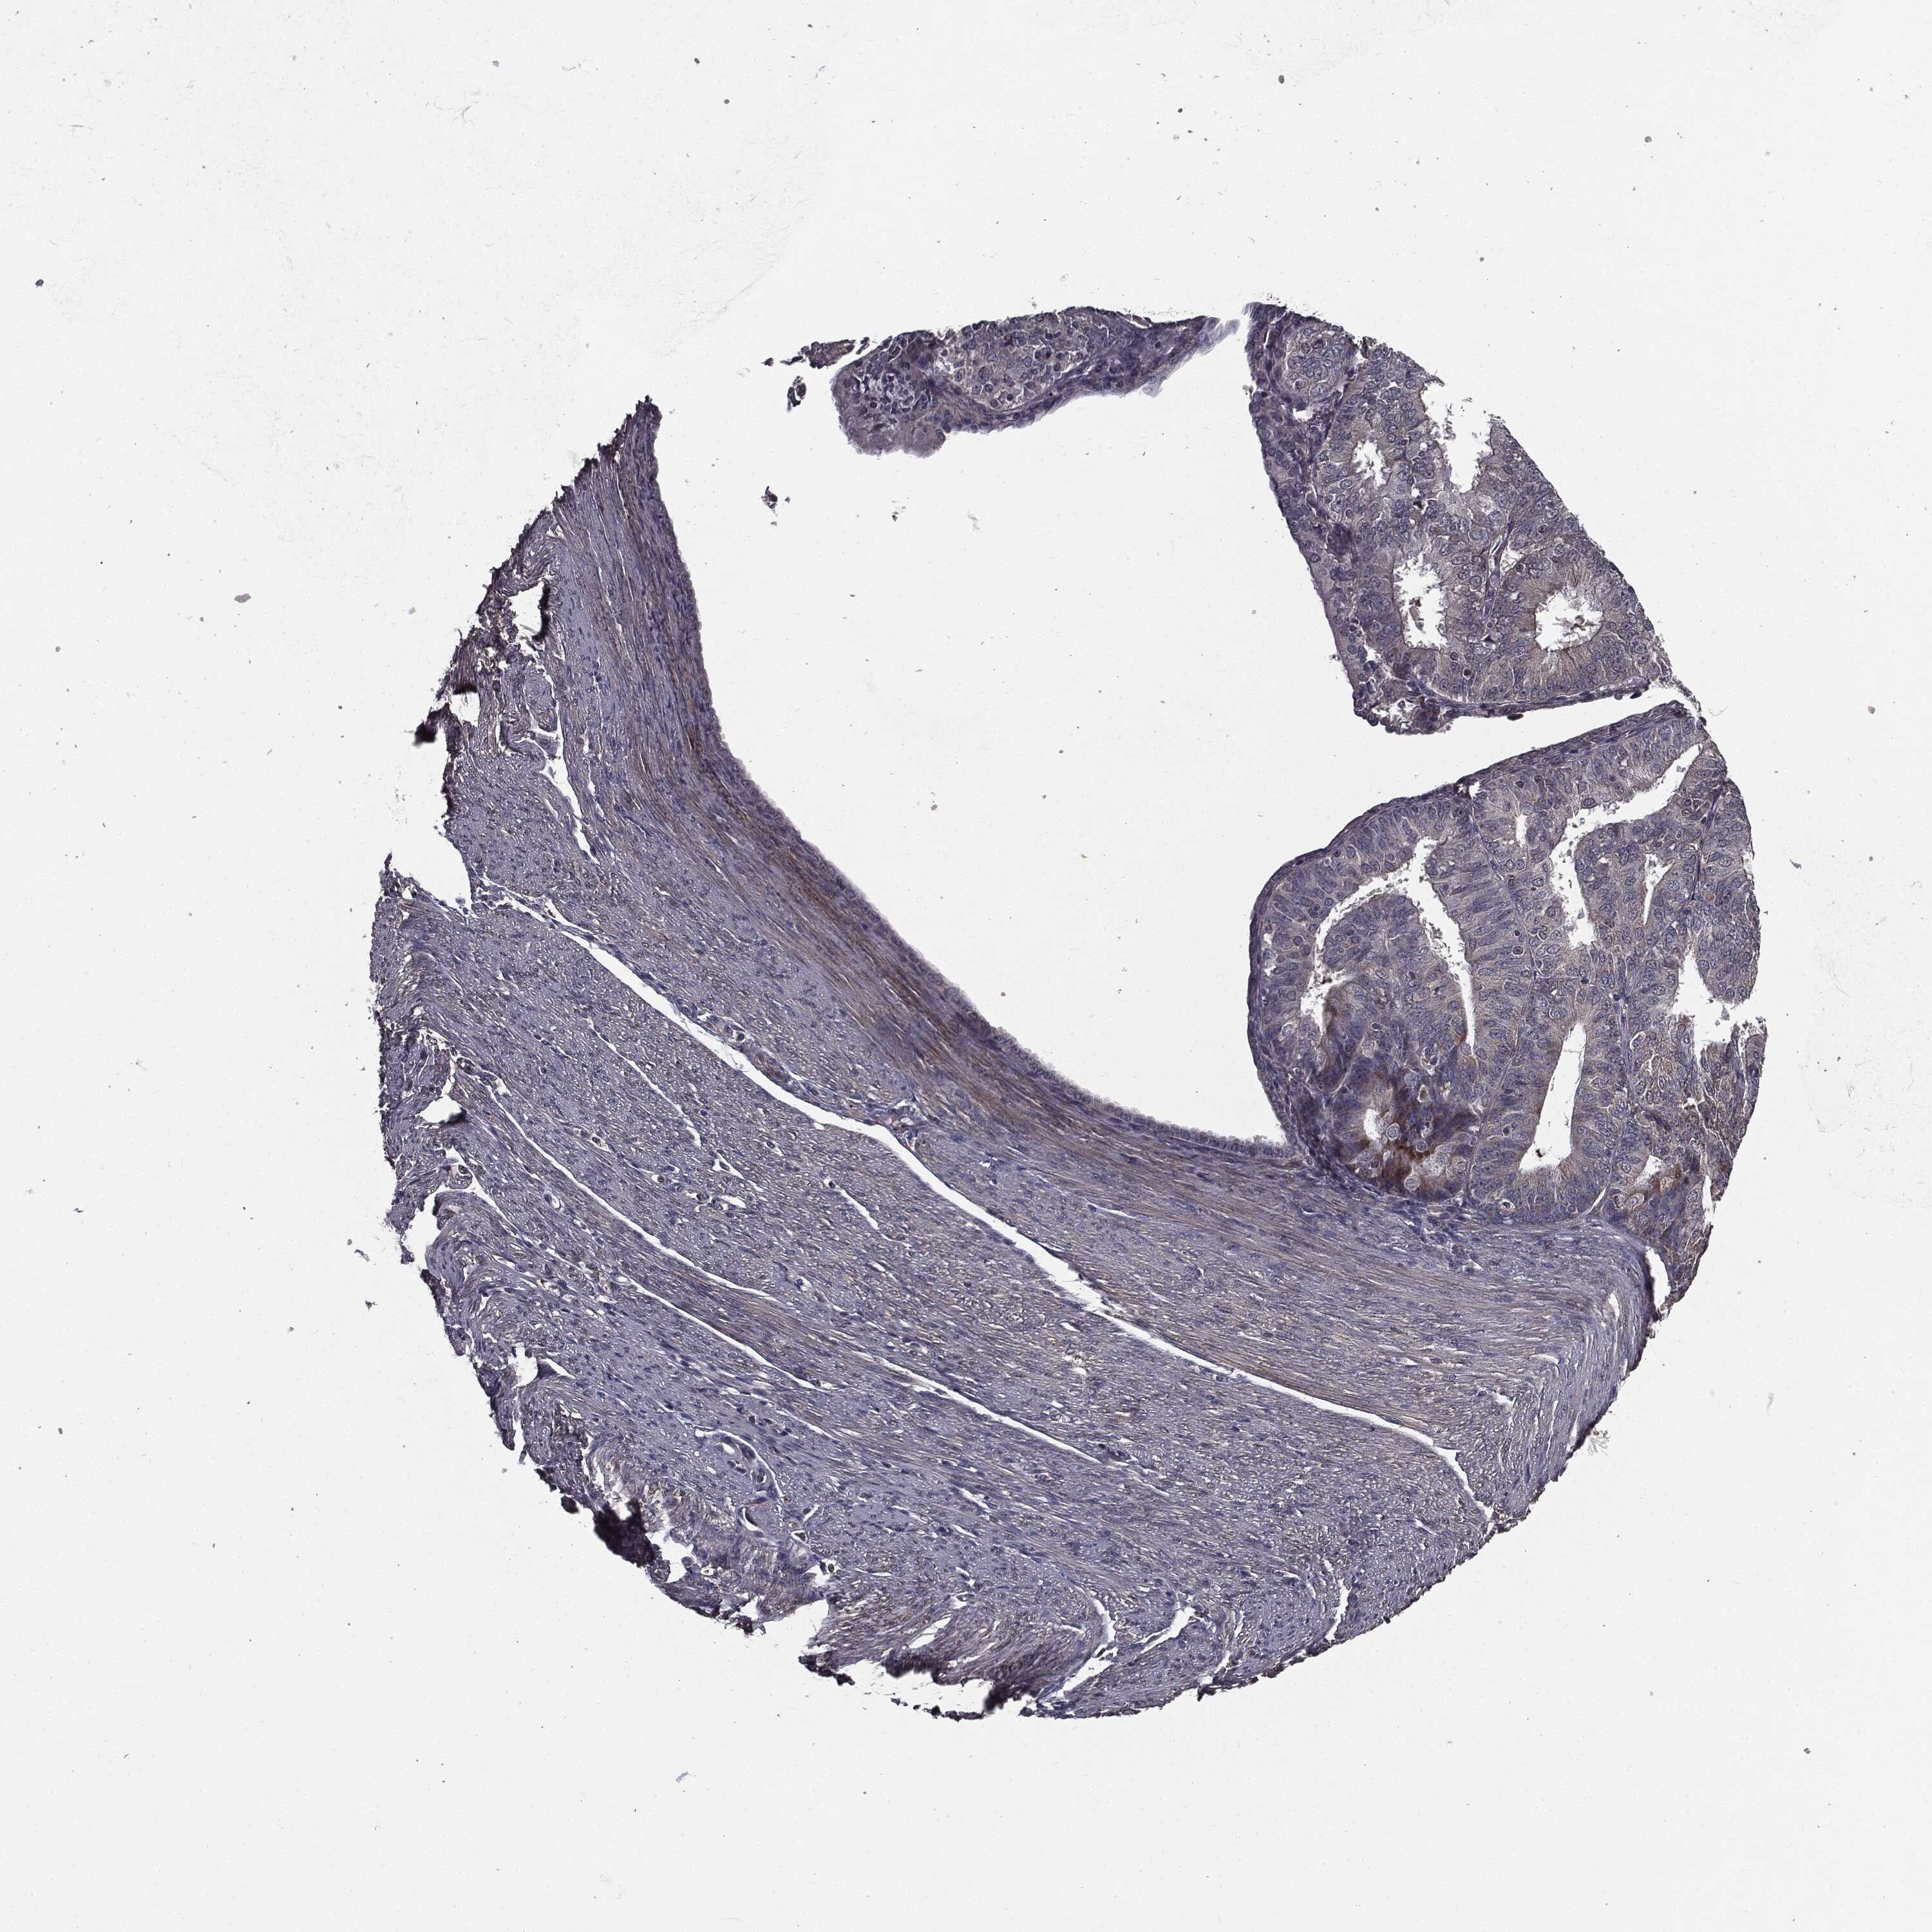

ENDOMETRIAL CANCER - Protein expressioni

A mouse-over function shows sample information and annotation data. Click on an image to view it in a full screen mode. Samples can be filtered based on level of antibody staining by selecting one or several of the following categories: high, medium, low and not detected. The assay and annotation is described here.

Note that samples used for immunohistochemistry by the Human Protein Atlas do not correspond to samples in the TCGA dataset.

Antibody stainingi

Antibody staining in the annotated cell types in the current human tissue is reported as not detected, low, medium, or high, based on conventional immunohistochemistry profiling in selected tissues. This score is based on the combination of the staining intensity and fraction of stained cells.

Each image is clickable and will lead to virtual microscopy that enables deeper exploration of all samples and also displays staining intensity scores, fraction scores and subcellular localization as well as patient and tissue information for each sample.

Antibody HPA052606

Antibody HPA077139

Staining

High

Medium

Low

Not detected

Intensity

Strong

Moderate

Weak

Negative

Quantity

>75%

75%-25%

<25%

None

Location

Nuclear

Cytoplasmic/membranous

Cytoplasmic/membranous,nuclear

Adenocarcinoma, NOS